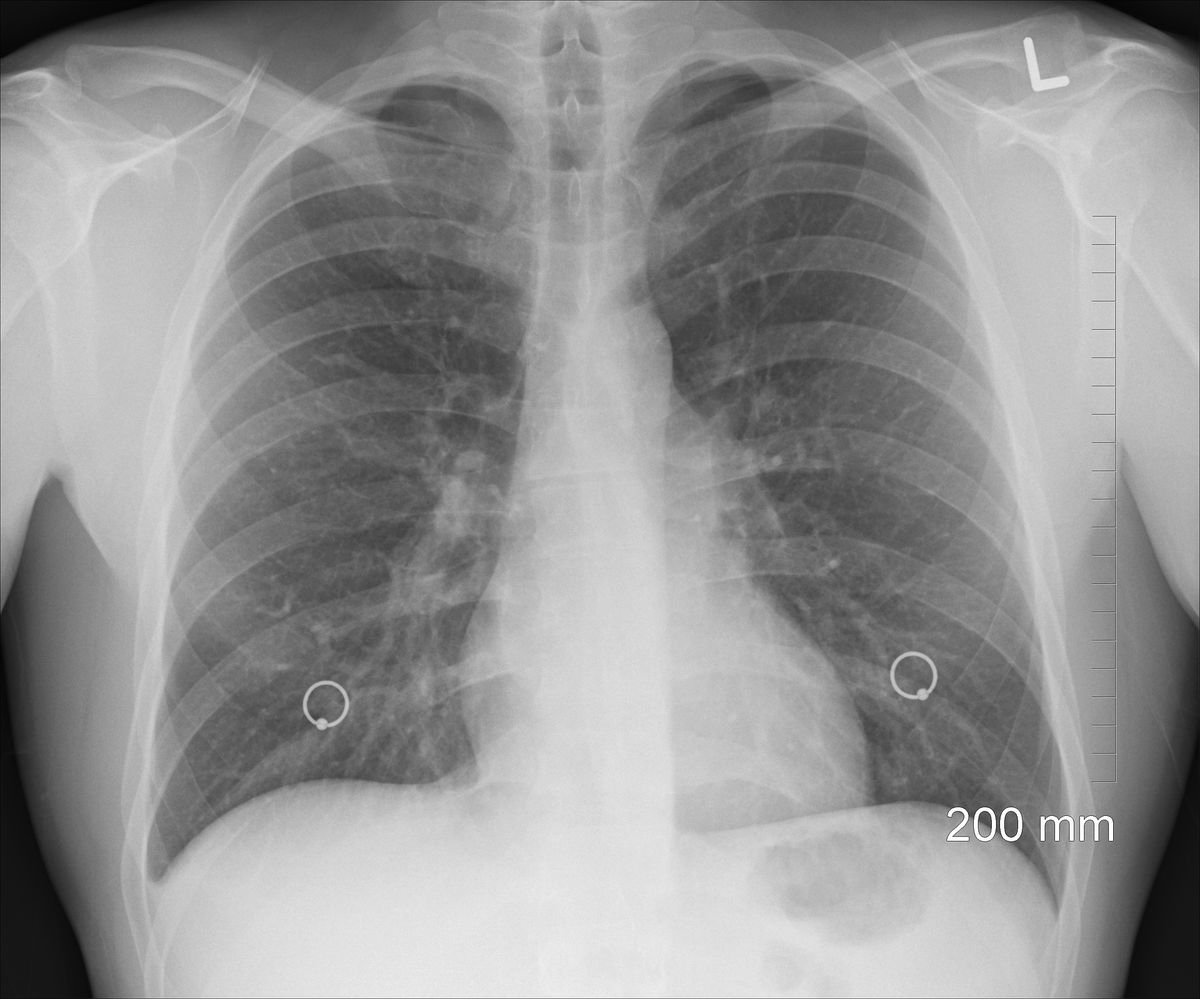

– Wyniki badań klinicznych pokazują, że immunoterapia przynosi lepsze efekty

i jest lepiej tolerowana niż chemioterapia jednolekowa, co dla wielu chorych oznacza nie tylko dłuższe życie, ale też możliwość zachowania samodzielności

i większego komfortu codziennego funkcjonowania – zwraca uwagę dr n. med. Maciej Bryl, dyrektor Wielkopolskiego Centrum Pulmonologii i Torakochirurgii

w Poznaniu. - W badaniu IPSOS atezolizumab wykazał wyraźną przewagę nad klasyczną chemioterapią dzięki wyższej skuteczności i lepszemu profilowi bezpieczeństwa. Mediana przeżycia była istotnie dłuższa, a odsetek pacjentów żyjących po dwóch latach ponad dwukrotnie wyższy niż w grupie leczonej chemioterapią. Co ważne atezolizumab może być podawany zarówno

w typowych infuzjach dożylnych trwających od 30 do 60 min, w różnych schematach dawkowania, jak i postaci krótkich iniekcji podskórnych, co ma szczególne znaczenie u pacjentów starszych u których dostęp dożylny jest utrudniony. Mam nadzieję, że już niebawem będziemy go mogli również stosować w monoterapii u pacjentów niekwalifikujących się do leczenia standardową chemioterapią opartą o pochodne platyny. Dziś to jedna z najbardziej potrzebujących i niezaopiekowanych grup pacjentów z rakiem płuca – dodaje.

Obecnie w Polsce leczenie chorych na niedrobnokomórkowego raka płuca w pierwszej linii z ekspresją PD-L1 poniżej 50% jest możliwe jedynie w skojarzeniu z chemioterapią opartą o pochodne platyny.

- Możliwość zastosowania immunoterapii w monoterapii u pacjentów z przeciwwskazaniami do chemioterapii opartej o pochodne platyny, wypełniłoby istotną lukę terapeutyczną i otworzyłoby nowe możliwości terapeutyczne zgodne z najnowszą wiedzą medyczną dla tej wąskiej grupy chorych, dając szansę na dłuższe, dobrze tolerowane leczenie i lepszej jakości życie. Każdy pacjent na to zasługuje bez względu na wiek, miejsce zamieszkania, czy status materialny. Warto o tym przypominać nie tylko w listopadzie – miesiącu świadomości raka płuca – dodaje Aleksandra Wilk.